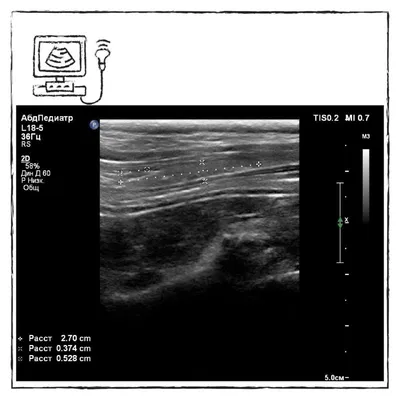

👍Напомню про давно, но хорошо отснятое видео🔍: https://dzen.ru/video/watch/6312f3ff684dd04098ab3691 🎠Кстати, как вам состояние щитовидной железы у собаки из карусели❓ #УЗИ #гипотиреоз